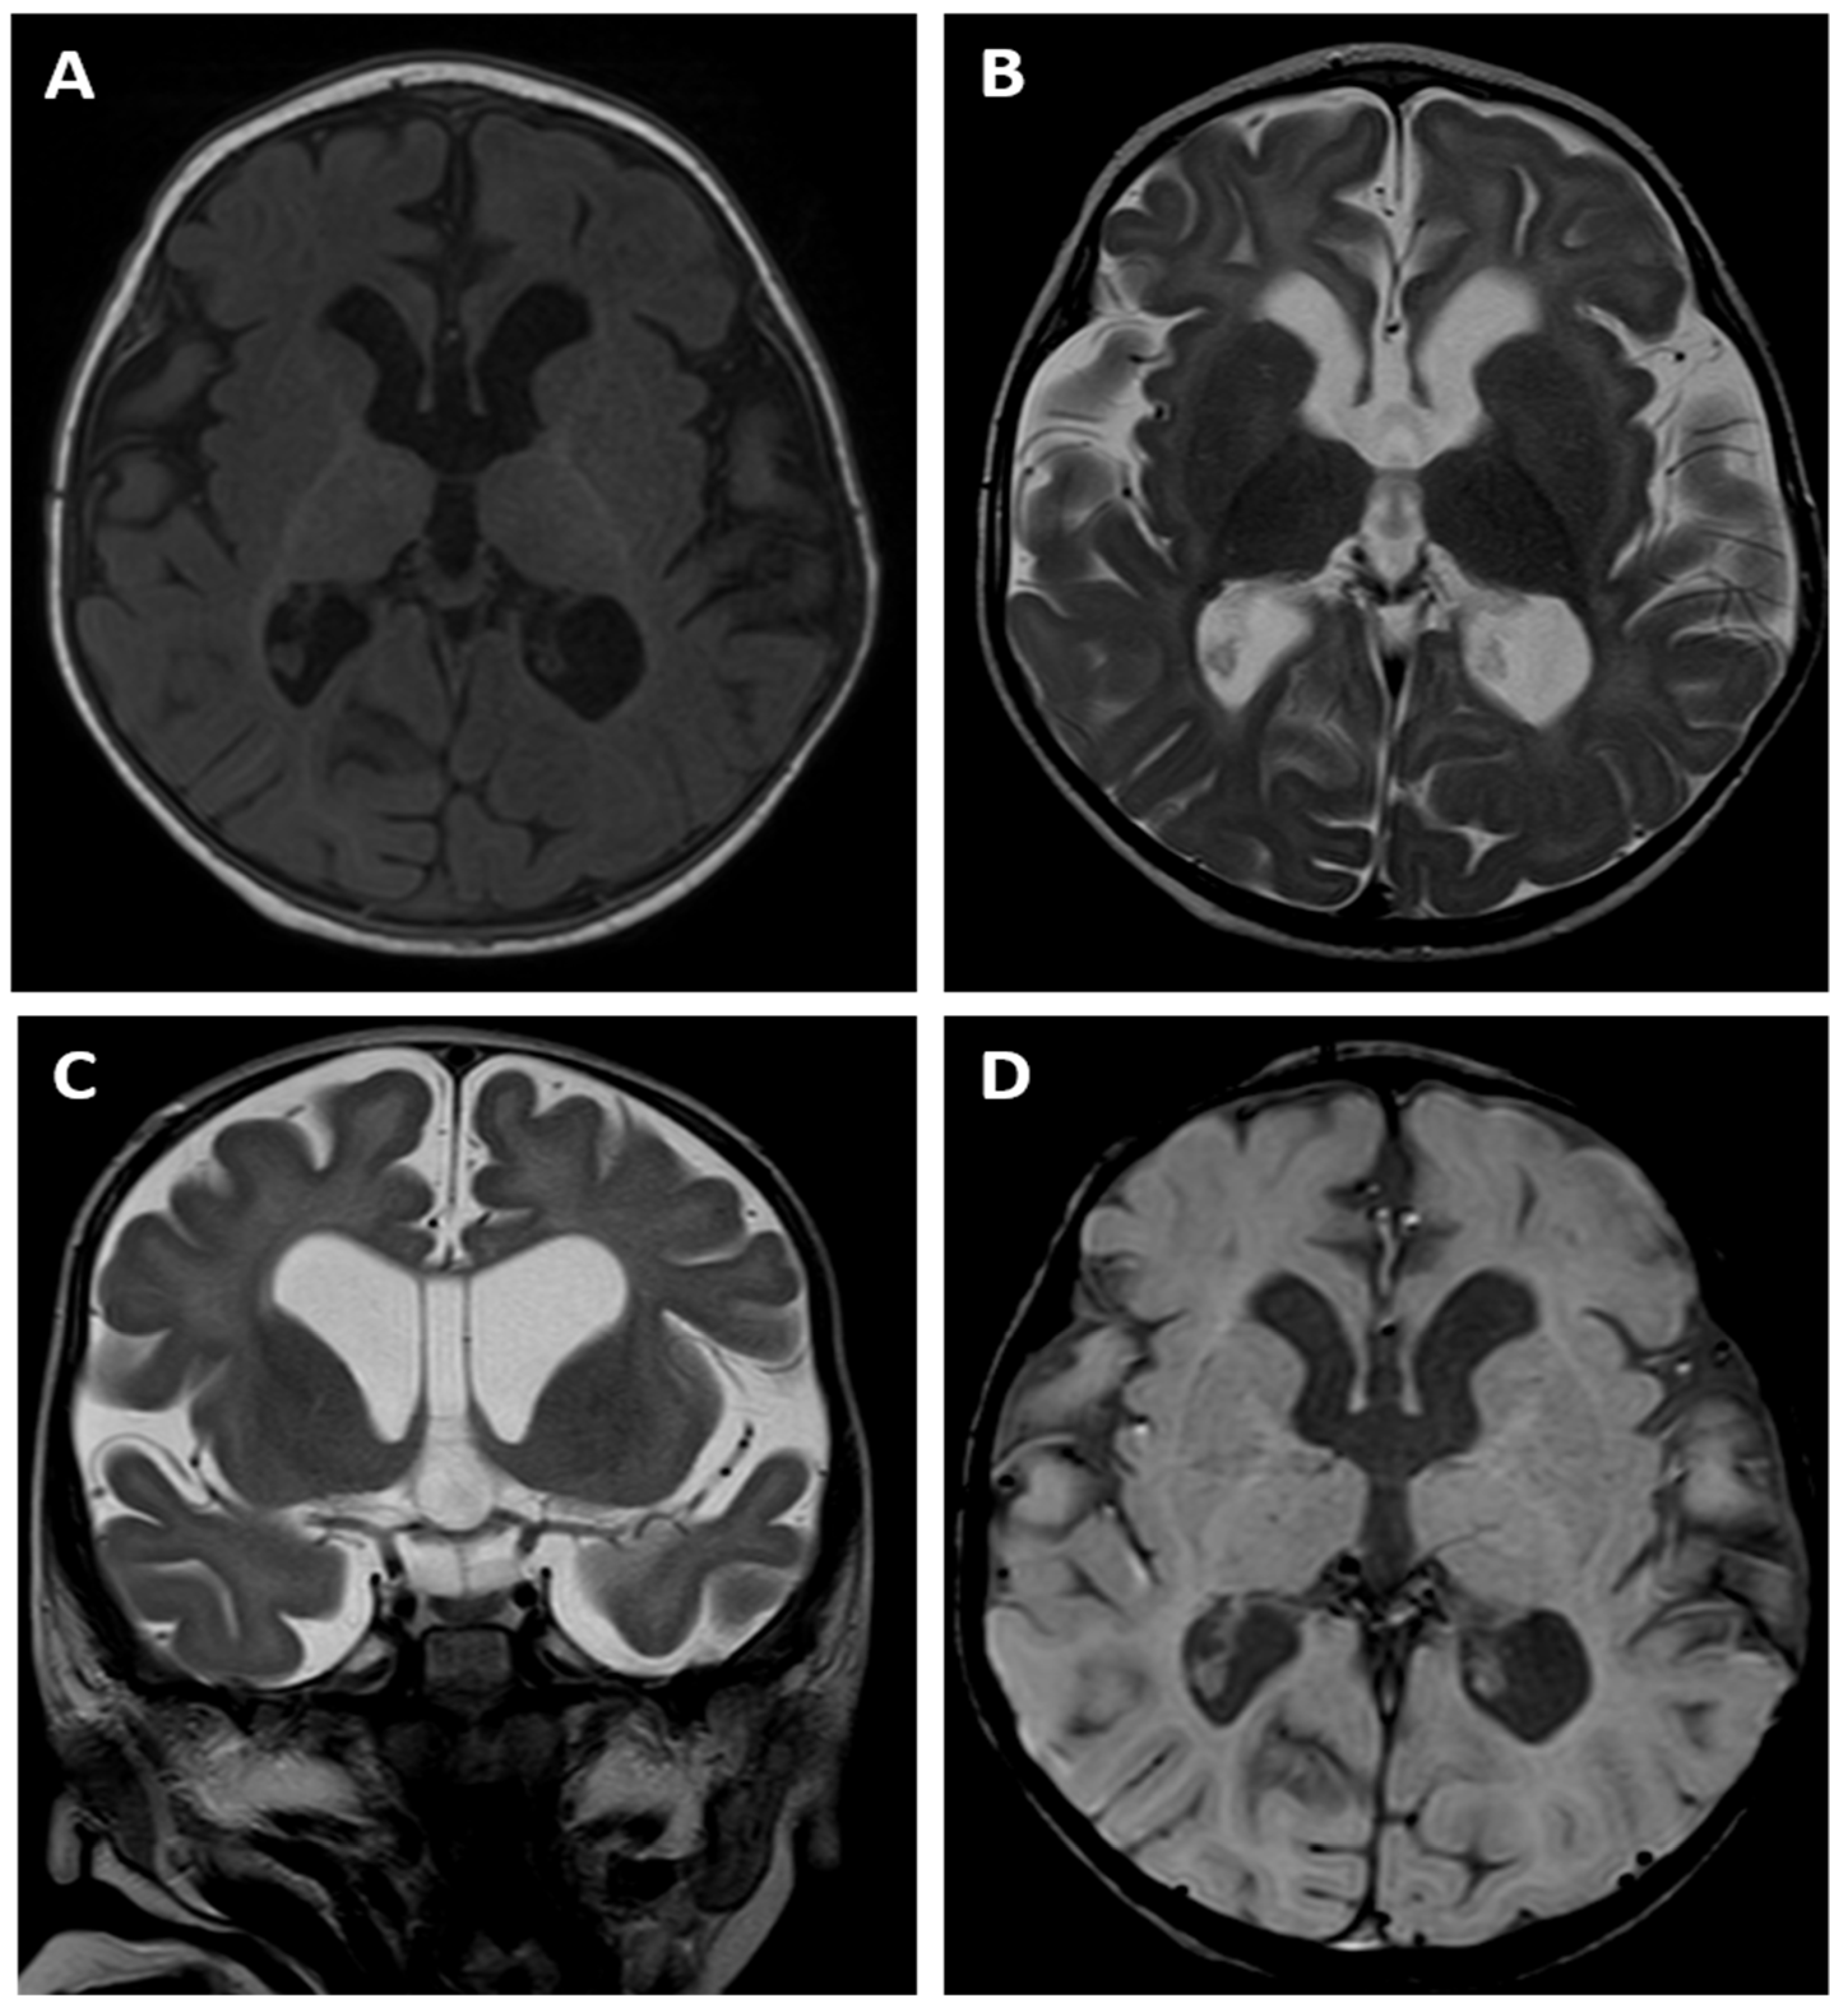

A brain MRI examination performed at the age of 14 months revealed an absence of normal myelination according to the age of the child. The T1- and T2-weighted images (Figure 3A,B) suggested delayed myelination of the cerebral white matter. The MRI appearance indicated a stage of myelination that was typical for the age of 8 months as there was a pronounced difference between the “anterior” and “posterior” parts of the brain, which was visible on the T1-weighted image with a lower signal within the former one. However, cortex/white matter differentiation could be detected instead of being blurred, which is a typical finding of a normal myelination process, meaning that a dysmyelination disorder should be suspected in this child.

There was also dilatation of the lateral ventricles, the third ventricle and the cerebral sulci as a sign of cerebral cortico-subcortical atrophy. The MRI also showed a cavum septum pellucidum, which is a normal variant of the CSF space, between the leaflets of the septum pellucidum (Figure 3C). The SWI sequence (Figure 3D) did not reveal any low signal of hemosiderin depositions, which meant that there were no signs of any previous intracranial bleeding, including intraventricular haemorrhage (IVH).

One of the most severe issues of proband 2 are the pathologies in her brain, as revealed by the MRI examination performed at the age of 14 months. The brain MRI showed an absence of normal myelination according to the age of the child, which suggested delayed myelination of the white matter and indicated a stage of myelination typical for the age of 8 months. There was also dilatation of the lateral ventricles, the third ventricle and the cerebral sulci as a sign of cerebral cortico-subcortical atrophy.

The clinical picture suggests two main causes for these disorders: hypoglycaemia and the presence of the ZMYND11 mutation. In the case of both diagnoses, CNS abnormalities of various morphologies are very common. In the case of hypoglycaemia, disturbances in the structure of the cerebral cortex are described in the literature, including advanced destructive changes in the white matter and dilatation of the ventricular system [28,29], which are consistent with the MRI image of our patient. In addition, intraventricular haemorrhage (IVH) reported by two centres [30,31], both occurring within the first 10 days of life, seems to be associated with HH, but not in the proband presented in this paper, as we did not observe any low signals of hemosiderin depositions in the SWI sequence. We believe that the vanishing syndrome (VWM) is worth mentioning in the context of the described proband, although the typical MR appearance of white matter alterations in the VHM syndrome is completely different. The characteristic MRI findings of VWM include diffuse, symmetric cerebral white matter involvement with T2 and FLAIR high-signal-intensity areas, which extend from the periventricular regions to the subcortical arcuate fibres. Over time, the white matter vanishes and is replaced by characteristic areas presenting almost CSF signal intensity, which means low signal changes on FLAIR images [32]. Cerebellar atrophy is also present in VWM, being the only similar feature regarding the white matter MR appearance in patients with VWM and in our patient.

Moving onto neurological disorders in cases with ZMYND11 pathological variants, their range is immensely wide and includes generalised developmental delay, seizures, autism and behavioural abnormalities [6,7,11]. Among them, the presented patient 2 suffers from generalised developmental delay and seizures, which were diagnosed at 2 months of age. We believe that the ZMYND11 mutation also seems to have a significant impact on dysmyelination changes in the presented probands, which is confirmed by scientific reports. Cortico-subcortical atrophy of the cerebral cortex [1], cerebral atrophy, delayed myelination and compression of myelin [5,7,11] are MRI findings that have been reported in the papers published hitherto. These vastly coincide with the changes exhibited by our probands.

Figure 3. Brain MR examination of patient 2: axial T1-weighted image (A), axial (B) and coronal (C) T2-weighted images, as well as SWI image (D). The T1- and T2-weighted images (AC) suggest delayed myelination of the cerebral white matter, indicating a stage of myelination typical for the age of 8 months. There is also dilatation of the ventricular system and cerebral sulci as a sign of cerebral cortico-subcortical atrophy. The MRI also showed a cavum septum pellucidum (C). The SWI sequence (D) did not reveal any low signals of hemosiderin depositions.